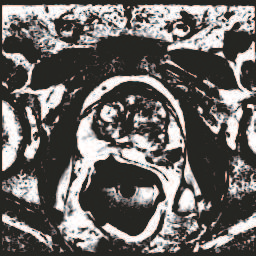

In this paper, we focus on three problems in deep learning based medical image segmentation. Firstly, U-net, as a popular model for medical image segmentation, is difficult to train when convolutional layers increase even though a deeper network usually has a better generalization ability because of more learnable parameters. Secondly, the exponential ReLU (ELU), as an alternative of ReLU, is not much different from ReLU when the network of interest gets deep. Thirdly, the Dice loss, as one of the pervasive loss functions for medical image segmentation, is not effective when the prediction is close to ground truth and will cause oscillation during training. To address the aforementioned three problems, we propose and validate a deeper network that can fit medical image datasets that are usually small in the sample size. Meanwhile, we propose a new loss function to accelerate the learning process and a combination of different activation functions to improve the network performance. Our experimental results suggest that our network is comparable or superior to state-of-the-art methods.